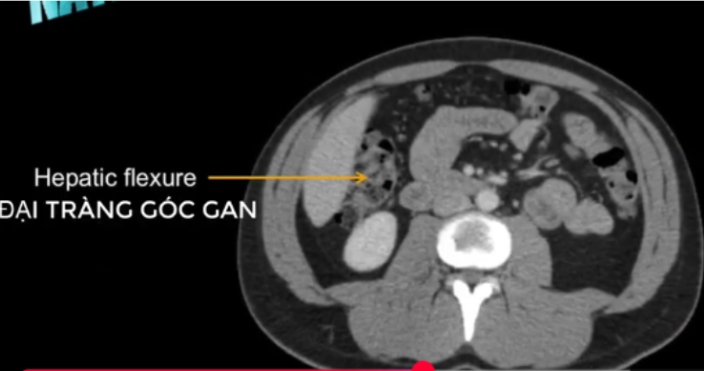

ĐT góc gan?